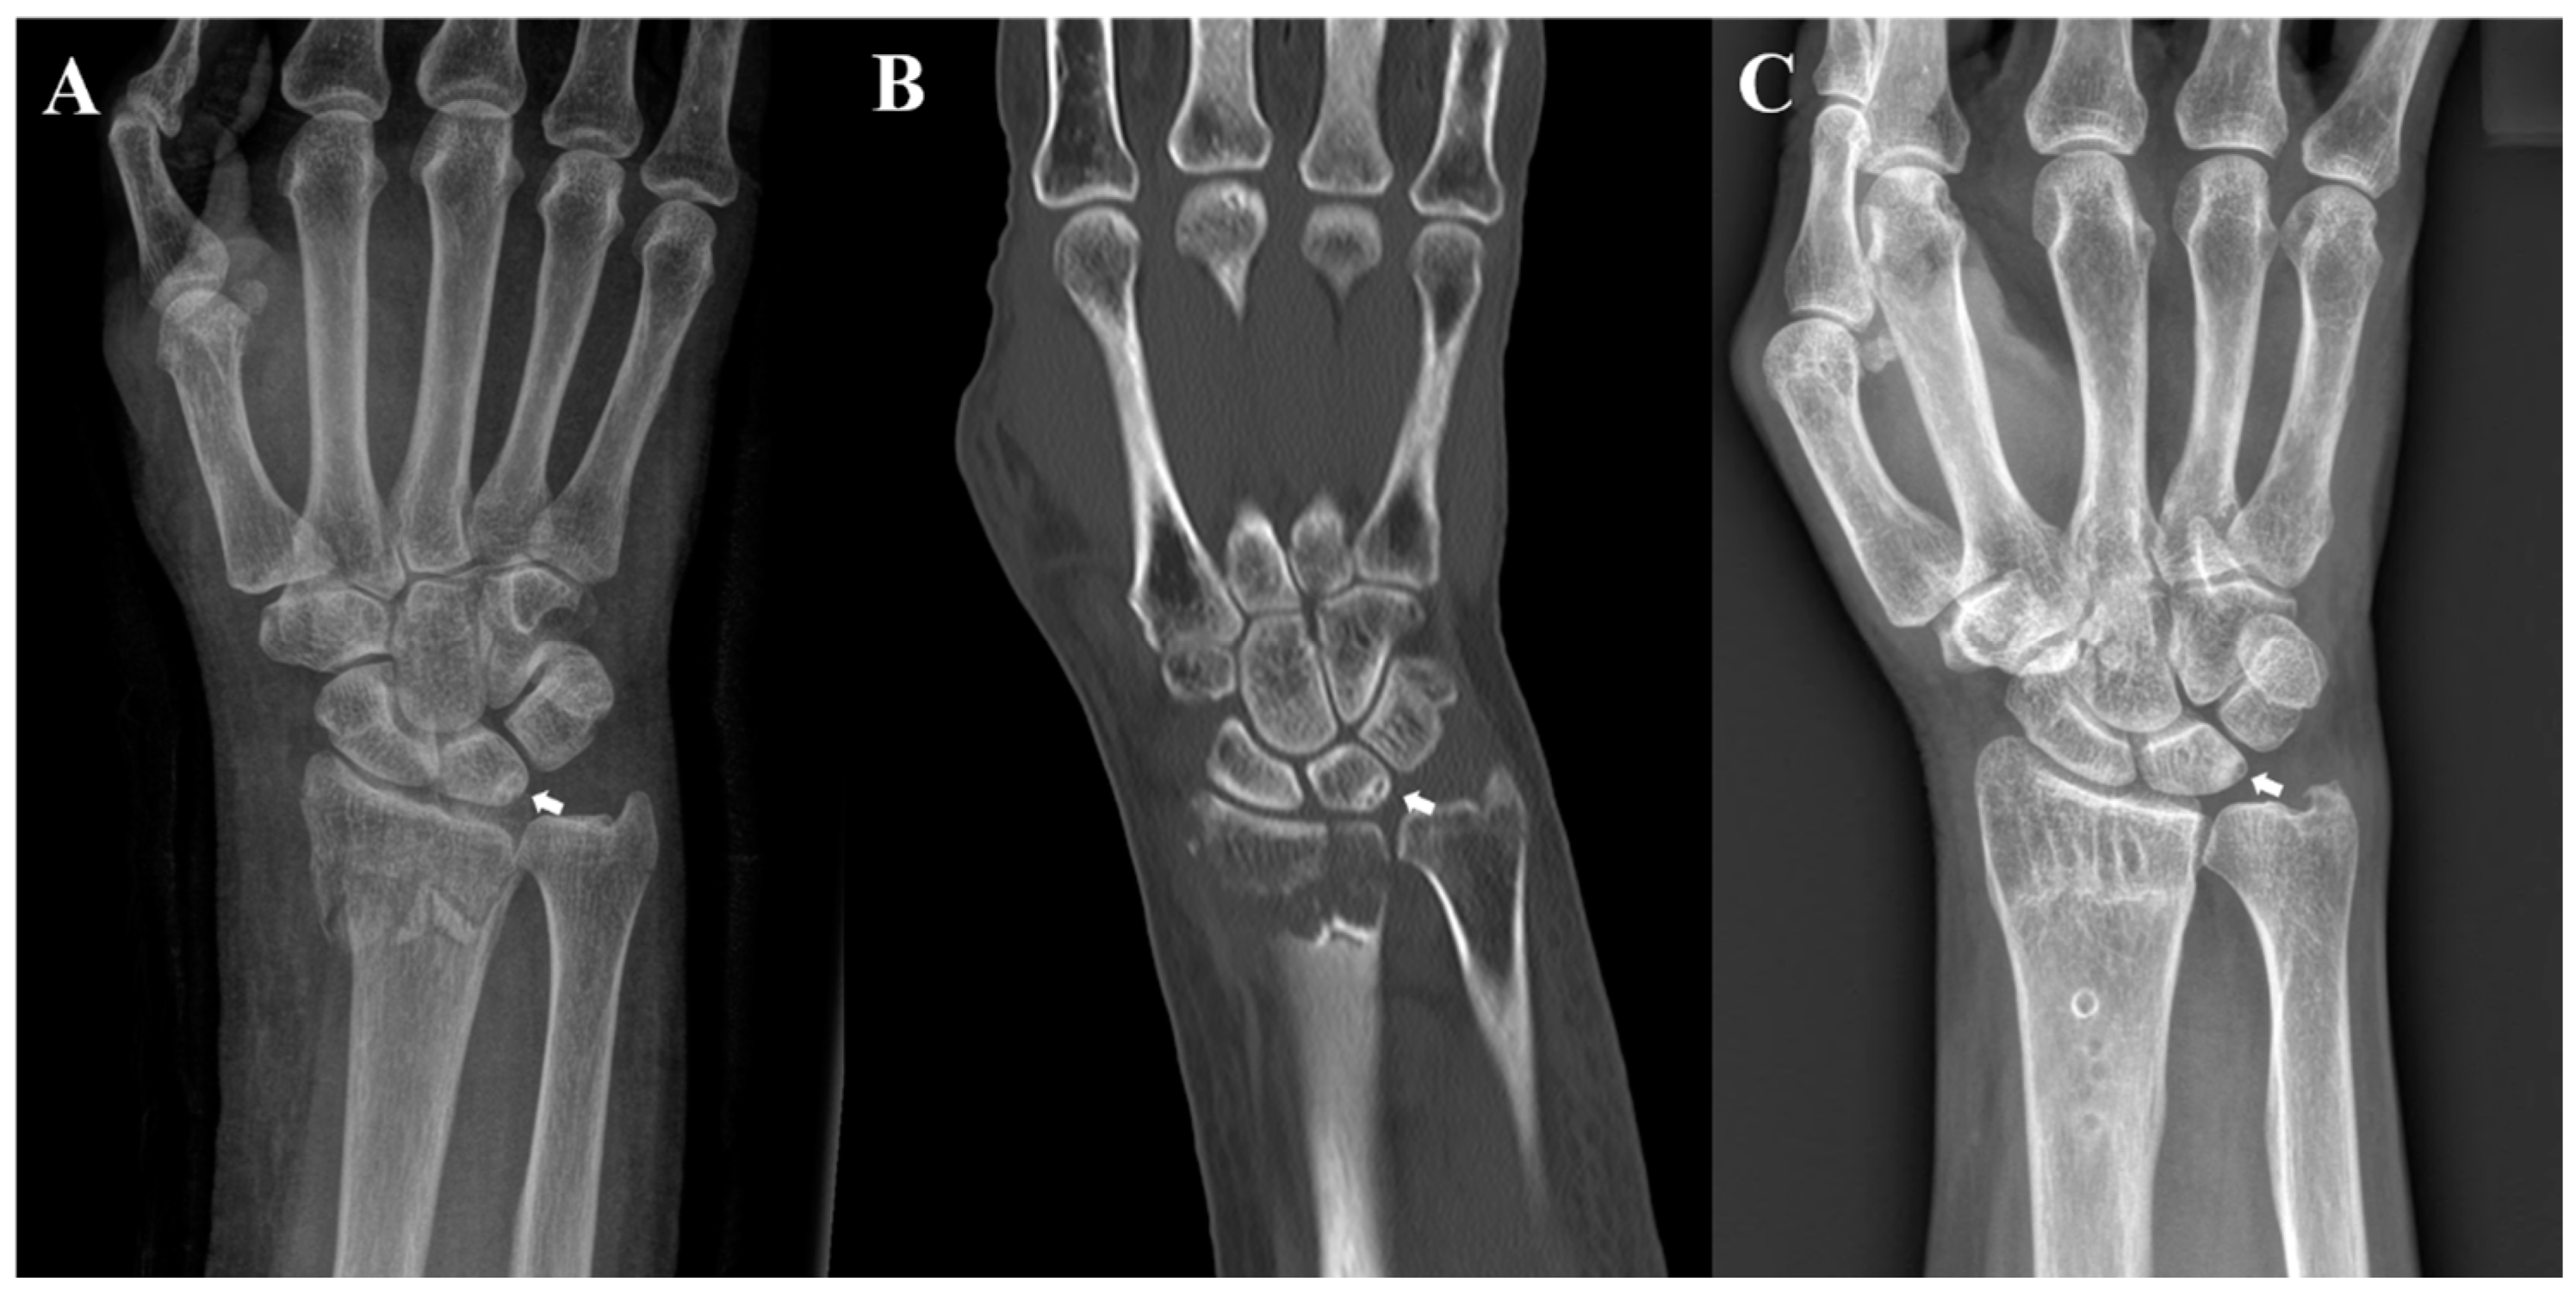

Ulnar-Sided Sclerosis of the Lunate Does Not Affect Outcomes in Patients Undergoing Volar Locking Plate Fixation for Distal Radius Fracture

:1. Introduction